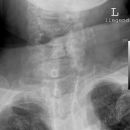

Deckplatte LWK 2 ohne Hinterkante